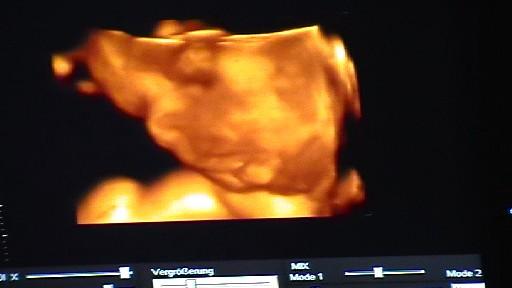

@Vroni: bin ja schon so gespannt auf deinen Ultraschall..... aber das dauert ja leider noch....